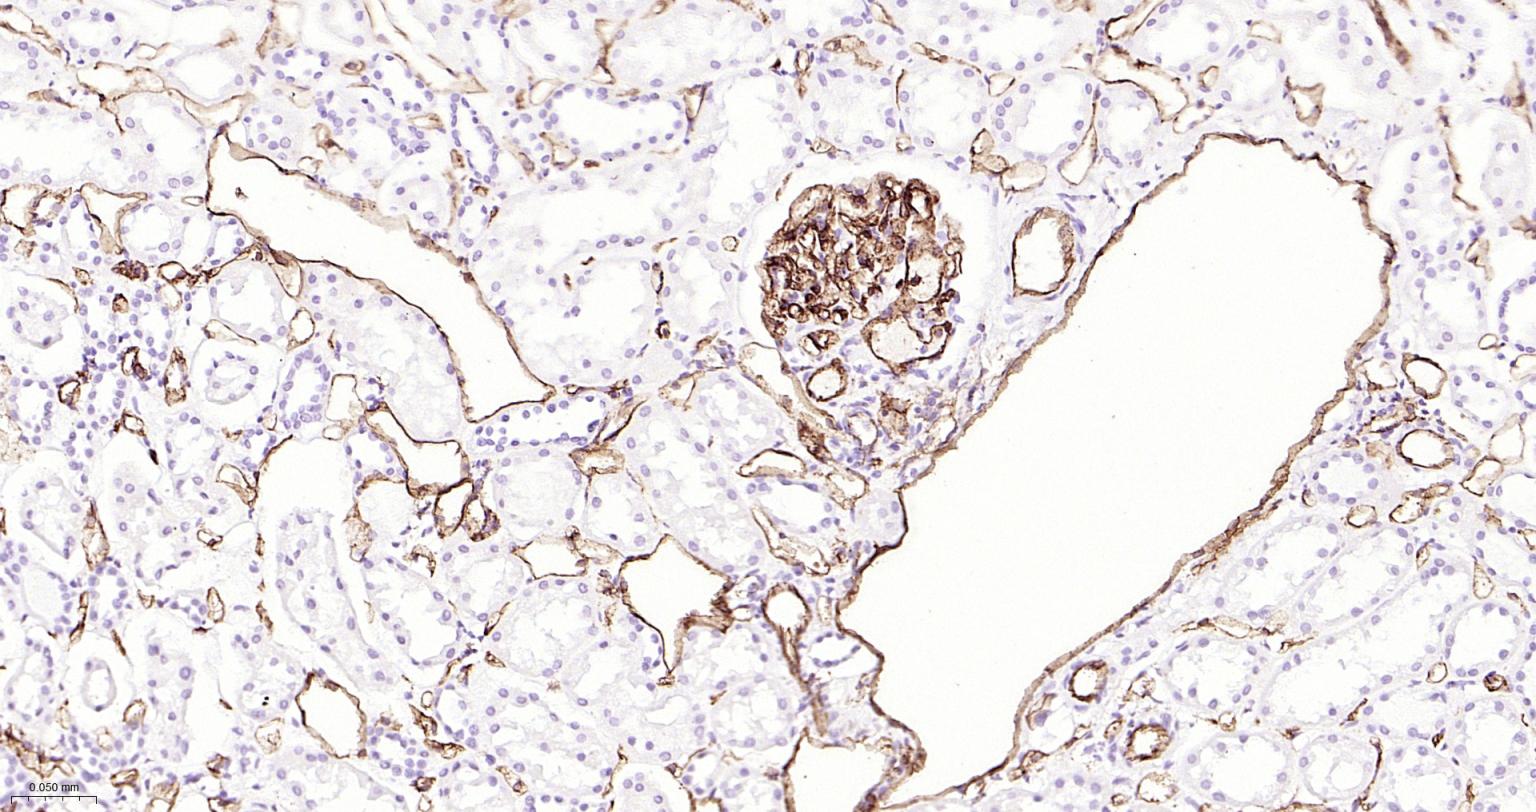

| IHC-P | Human | 1:200-2000 | |

Expressed on platelets and leukocytes and is primarily concentrated at the borders between endothelial cells (PubMed:18388311, PubMed:21464369).

Expressed in human umbilical vein endothelial cells (HUVECs) (at protein level) (PubMed:19342684, PubMed:17580308).

Cell adhesion molecule which is required for leukocyte transendothelial migration (TEM) under most inflammatory conditions (PubMed:19342684, PubMed:17580308).